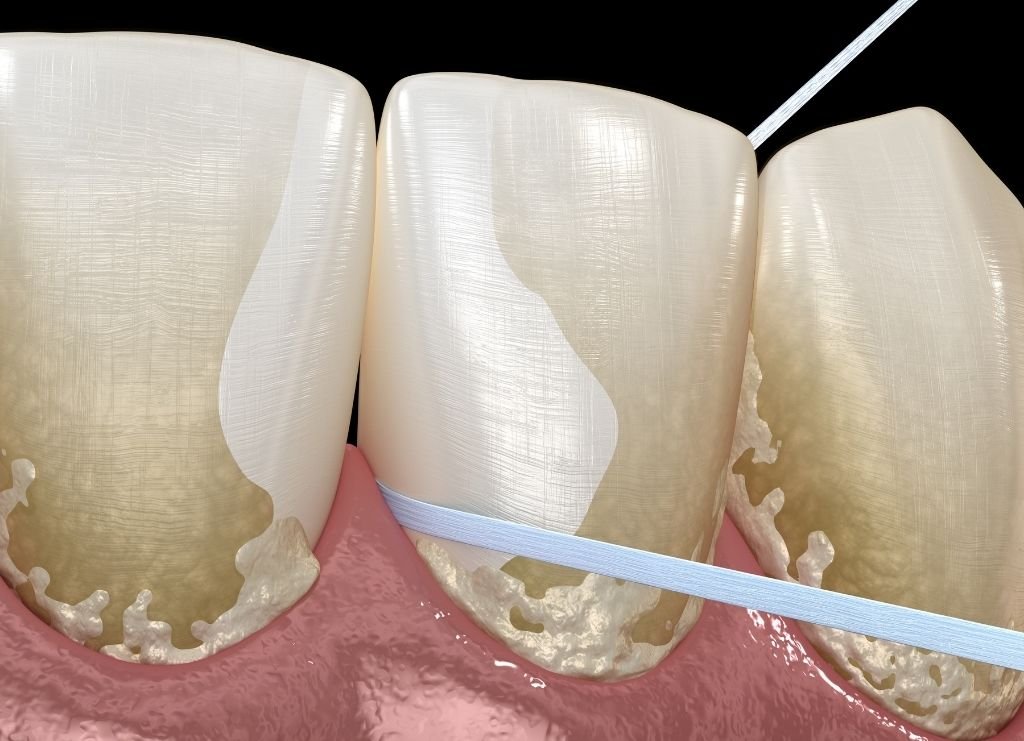

Tratamentos gengivais

Dentro desta categoria, existem diversos tratamentos que o podem ajudar a melhorar a sua estética dentária, tais como as plásticas gengivais, a destartarização (limpeza) e a despigmentação/aclaramento gengival.

Como a gengiva e o osso alveolar são o que apoia os nossos dentes, a saúde deles tem um grande impacto no desenvolvimento do nosso sorriso, e ao efetuarmos os tratamentos descritos anteriormente, estamos a contribuir para estes tecidos tão essenciais continuarem saudáveis.

Também existem tratamentos que o podem ajudar a melhorar o seu contorno gengival que são realizadas a laser, e por vezes isto é o suficiente para melhorar um pouco mais a estética do seu sorriso. Podemos ainda ajudar a clarear a cor das suas gengivas através da utilização de laser, que é uma técnica simples e indolor, e que pode melhorar exponencialmente o aspeto do seu sorriso no panorama geral.